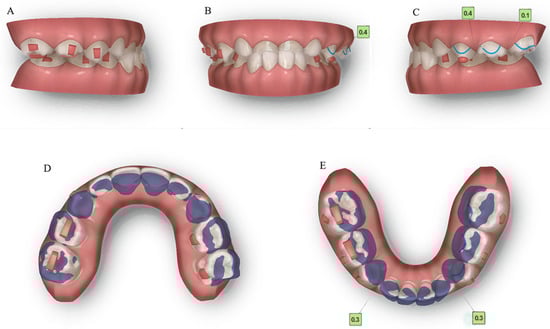

2.4. Treatment Progress

We used ClinCheck® (Align Technology, San Jose, CA, USA) to plan tooth movement virtually in three dimensions (depicted in Figure 9). The ellipsoid and optimized attachments on teeth 63 and 85 promoted retention. The rectangular attachments on the occlusal surfaces of teeth 54, 55, 84 and 85 increased the vertical height to unlock the scissor bite. On the left side, the extent of the scissor bite was more severe than on the right side; therefore, we placed rectangular attachments on the lingual surfaces of the upper left deciduous molars and buccal surfaces of the lower molars. Meanwhile, a button cutout was designed for the upper left buccal and lower lingual deciduous molars, utilizing the interaction traction with elastics. Overall, the upper posterior segments moved lingually, while the lower counterparts moved buccally to resolve the dental arch discrepancy, and thus alleviate the scissor bite. Furthermore, the upper anterior teeth were proclined, while the lower teeth progressively moved to alleviate the anterior crossbite, placing the bilateral condyles into centric relation.

Figure 9. Pre-treatment ClinCheck® models and ClinCheck® treatment plan. (A): Lateral view of the right side of the pre-treatment model; (B): frontal view of pre-treatment model; (C): lateral view of the left side of the pre-treatment model; (D): occlusal view of superimposition of pre-treatment (blue) and post-treatment (white) maxillary arch models; (E): occlusal view of superimposition of pre-treatment (blue) and post-treatment (white) mandibular arch models.